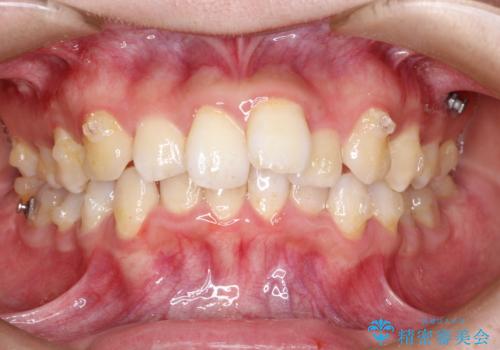

重度のガタガタのインビザラインによる非抜歯矯正

- 全体的なガタガタを気にされて来院されました。

抜歯矯正も考えられる状態でしたが、ご本人的になるべく歯を抜かない矯正を希望されました。

奥歯を後方に移動させるのと、歯と歯の間にわずかに隙間を作ることでスペースを確保して、抜歯をせず歯を並べる計画としました。

ガタガタの度合いが大きかったので少し時間がかかりましたが、非常に協力的な患者様でしたので、抜歯をせず計画通りに治療を終えることができました。